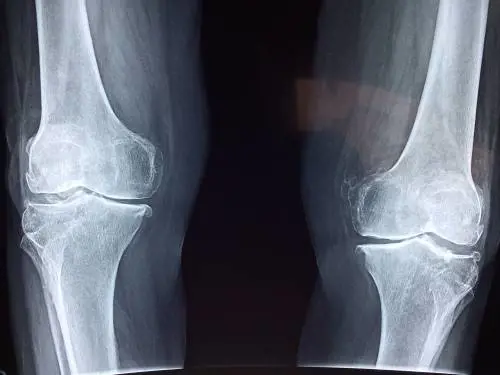

In costante evoluzione, di pari passo con la tecnologia delle apparecchiature utilizzate, l’attività del tecnico radiologo contribuisce ad individuare eventuali problematiche del paziente non riscontrabili con altri esami e mettere a punto la giusta terapia. Ma non solo. Vediamo formazione e guadagni